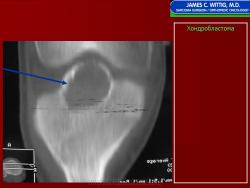

Рентгенологически хондробластома представляет собой сравнительно большой (2-4 см) очаг округлой формы, четко отграниченный от окружающей кости склеротической каймой. На фоне очага в большинстве случаев, но не обязательно определяются плотные включения, напоминающие хлопья ваты.

Рентгенологическая картина. Хондробластома выглядит как небольшой, от 3 до 6 см литический очаг, центрально или эксцентрично расположенный, с четкими контурами, занимающий около половины площади эпифизарной зоны. Хондробластома плоских костей и мелких трубчатых костей больших размеров, может сопровождаться припухлостью мягких тканей, вздутием кости и периостальной реакцией. Распространение процесса на метафизарную зону встречается часто.